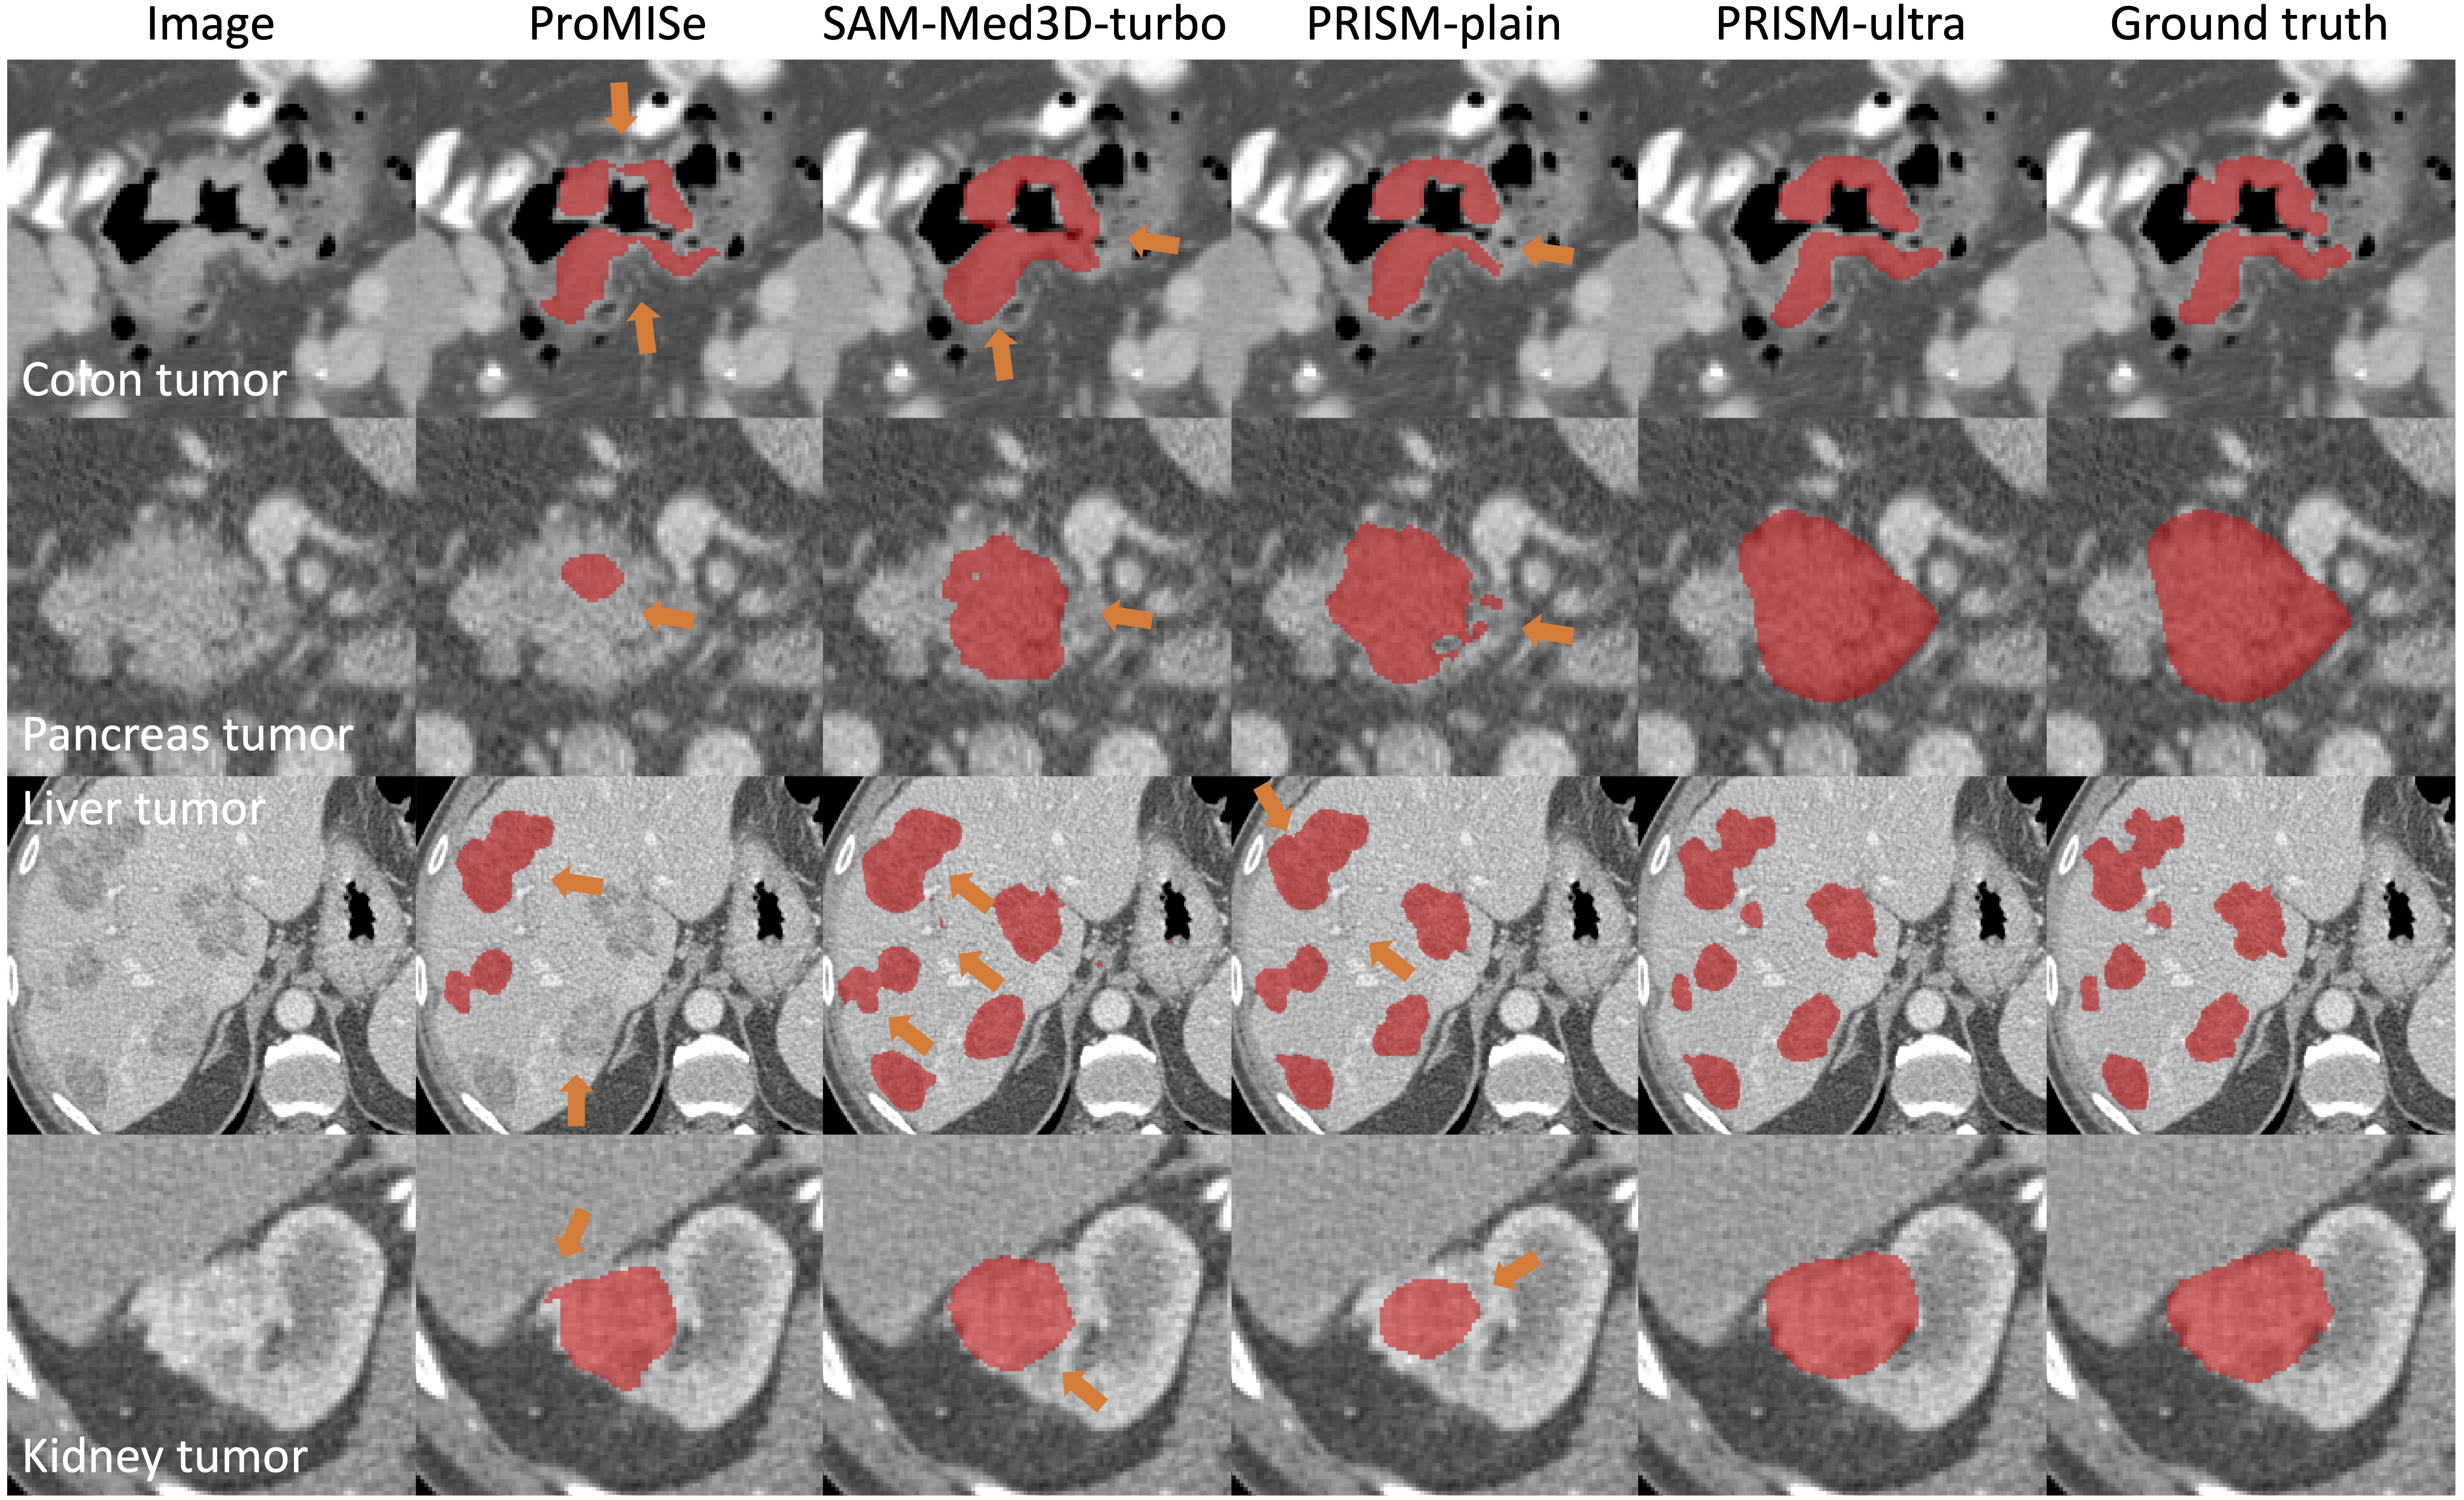

PRISM tumor segmentation examples

Briefly, PRISM produces tumor segmentation with mean Dice values of 93.79 (colon), 94.48 (pancreas), 94.18 (liver), and 96.58 (kidney).

| Qualitative results with compared methods | ![]() |